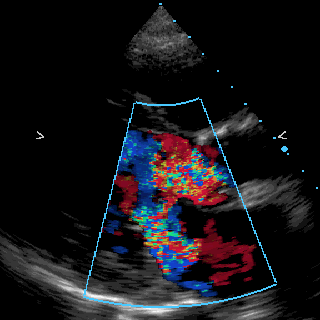

- The animated .gif image above was created from a QuickTime movie captured from the sample image "US-PAL-8-10x-echo.dcm" (a 10 frame DICOM Palette color US clip) that accompanies Madena.

- After opening this 10 frame image, Madena will be in "monochrome"

image display and processing mode. To recreate the example, switch to color display mode by clicking the RGB button.